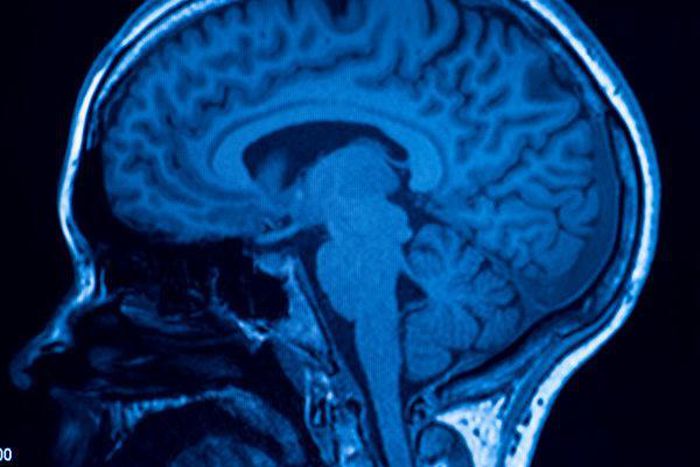

There is a well-defined biological response to stress, said Daniel Reisberg, a professor of psychology and perception at Reed College in Portland, Oregon. The body prioritizes resources and sharpens your focus to help you cope with stress.

The body activates a stress response mechanism, or the hypothalamic-pituitary-adrenal, or HPA, axis. This is a chemical sequence that starts with the hypothalamus in the forebrain, sending chemical signals to the pituitary, which then secretes the stress hormone ACTH, which then causes the adrenal glands to produce cortisol, experts said.

This is where memory comes into play.

The stress hormone cortisol causes a person to have tunnel vision in the extreme or a really narrow snapshot of what happened, Reisberg said. “When you’re under high stress, not only does it have an impact on how things are recorded in your brain but also how you can report on the memory,” he said.